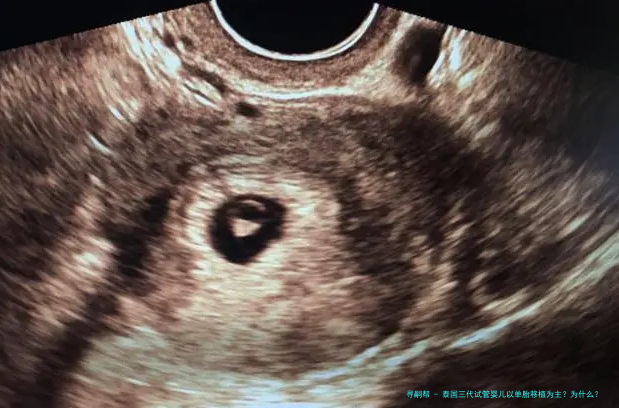

随着多个胎儿条件的放开,女年纪的增长,很多家庭去泰国做试管婴儿,因为要的是多胎,在进行胚胎移植的时候建议移植了一个胚胎。如此,泰国三代试管婴儿以单胞胎移植为主?为什么?下方跟随来一起了解一下吧。

泰国三代试管婴儿以单胎移植为主?为什么?

单胎移植、双胎移植具体情况具体分析,泰国医生并不是盲目建议试管婴儿家庭都进行双胎移植。

对于条件理想的患者,括移植2个有可能双胎妊娠的患者,或者因体重、子宫异常不能承受双胎妊娠的这么一部分患者,一般是建议进行单囊胚移植,既能保证她们的妊娠率,也能减低期的各种风险。

对于条件稍差的患者。比如:高龄、巢储备差,或者患子宫肌瘤、腺肌症等情况的患者,这些不利因素会影响胚胎着床率。那么,在这种情况下,会移植2个胚胎增加女方怀的机会。但,若是后期出现问题,从安全的因素考虑,请务必减胎。